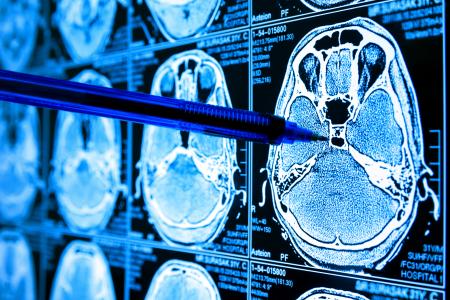

GLIOBLASTOME : Il affecte bien plus que le cerveau

Ces cancérologues de l’Albert Einstein College of Medicine (New York) viennent de découvrir un lien entre les tumeurs du cerveau, la boîte crânienne, la moelle osseuse du crâne et une perturbation du système immunitaire. Ces découvertes documentées dans la revue Nature Neuroscience, ouvrent la voie à une vision thérapeutique plus holistique.